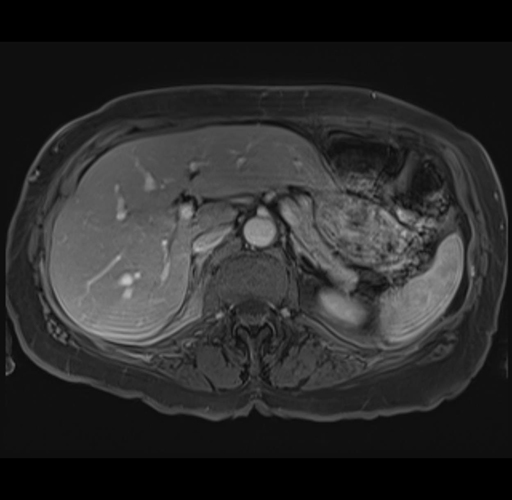

MRI T1

Imaging analysis